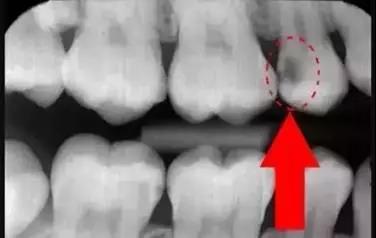

牙齿的牙根是埋在牙槽骨中的,医生没有透视眼,为了解患牙的牙根的形态、走向、长度及根尖周有无病变及病变大小,或者怀疑有肉眼无法确认的其它牙科问题,都会建议患者去牙科的X光,甚至,口腔CT来全面性地确认问题,以订定合适的治疗计划。

牙片(牙科X光)有助于牙医直接观察到普通口腔检查难以发现的牙齿和牙周组织问题,是早发现早治疗口腔问题的关键。希望大家一定要认识到牙片的重要性,拍片医生不是为了讹你钱,拍片没有很大的风险,大家不要担心!